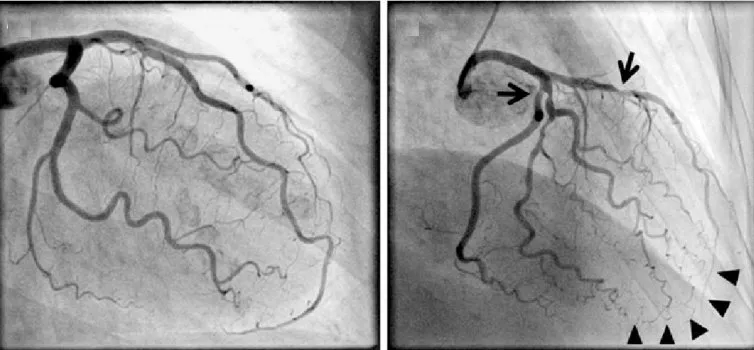

Để đánh giá tình trạng của stent và phát hiện sớm các biến chứng, chụp động mạch vành là phương pháp chẩn đoán tốt nhất. Chụp động mạch vành giúp bác sĩ quan sát trực tiếp lòng mạch và xác định xem stent còn tốt hay đã bị tắc, tái hẹp. Ngoài ra, bệnh nhân cũng cần chú ý đến các dấu hiệu bất thường và đến bệnh viện sớm hơn nếu có các triệu chứng như đau thắt ngực ngay cả khi nghỉ ngơi, tức ngực, khó thở hoặc mệt mỏi bất thường.